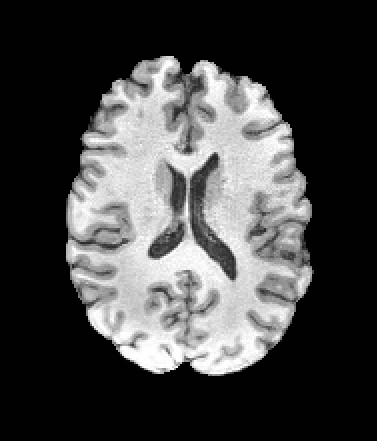

A trained MetaVoxel model can be unconditionally sampled by drawing Gaussian or categorical noise for each variable at timestep , and iteratively apply the denoising network until reaching . Unlike conventional diffusion models that focus solely on image generation, MetaVoxel can generate coherent synthetic patient profiles from the joint distribution , as shown in Figure 2.

| Age: 64.0 | Age: 53.8 | Age: 70.9 | Age: 76.9 |

| Sex: Male | Sex: Female | Sex: Female | Sex: Male |

![]() |

| Age: 80.9 | Age: 77.7 | Age: 73.2 | Age: 84.6 |

| Sex: Male | Sex: Female | Sex: Female | Sex: Female |